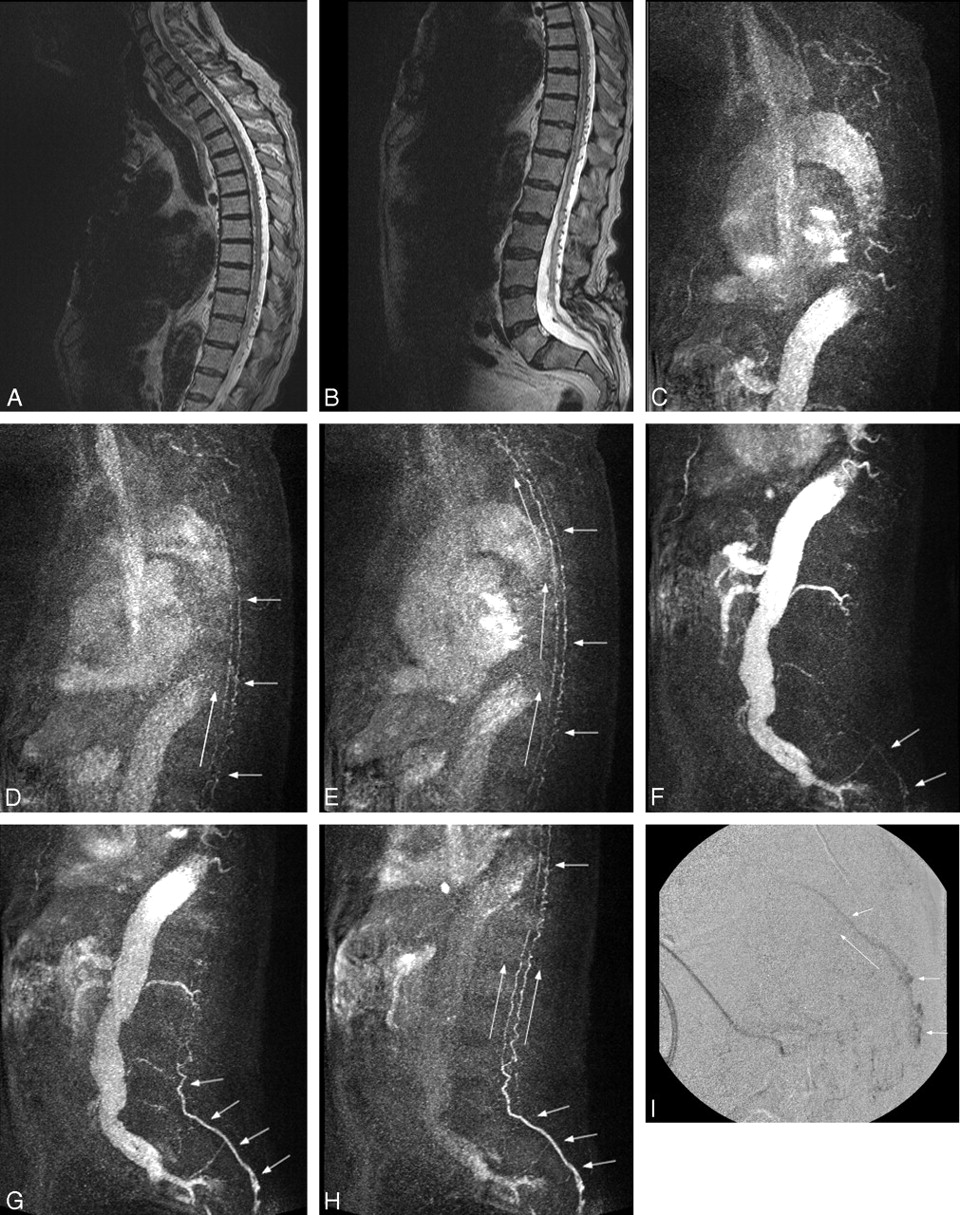

To further illustrate the utility of the technique, we describe 1 case in detail. Case 4 was a 73-year-old man who presented with progressive lower extremity weakness. Initial MR showed enlarged spinal veins from foramen magnum to sacrum and increased T2 signal intensity from level T8 through L4, findings highly suspicious for a spinal DAVF (Fig 1A, -B). TRSMRA localized the fistula in the left pelvis at approximately S3 (Fig 1C–H). Spinal DSA confirmed a sacral DAVF at the S4 level, and embolization was attempted (Fig 1I). At the end of the procedure, the dural fistula was seemingly obliterated. Five days later, a TRSMRA was performed that showed persistent arteriovenous shunting. Spinal DSA confirmed the residual fistula, and repeat embolization was unsuccessful. After surgical excision, postoperative TRSMRA showed no evidence of a persistent AV shunt.

A and B, Sagittal T2-weighted sequence in case 4 demonstrates serpiginous flow voids along the ventral and dorsal spinal cord from the cervical region to the sacrum. Increased T2-signal intensity is seen within the distal cord/conus. These findings are highly suspicious for a fistula, the level of which cannot be determined on these conventional images. The patient has incidental low-lying conus. C–E, Three MIP partitions from a sagittal TRSMRA (temporal resolution = 5.07 seconds) centered in the cervical and upper thoracic spine show early filling of venous structures on the ventral and dorsal surface of the cord (short arrows). Filling proceeds from caudal to cephalad (long arrows). F–H, Three MIP partitions from a sagittal TRSMRA (temporal resolution = 5.07 seconds) centered in the thoracic, lumbar, and upper sacral spine demonstrate early venous filling (short arrows) beginning within the pelvis and proceeding cephalad (long arrows). Unsubtracted images (not shown) showed the earliest venous drainage within the sacrum. A coronal oblique acquisition further localized the fistula to approximately the S3 level. I, Lateral projection from a superselective catheter spinal DSA shows early venous filling within the sacral canal proceeding cephalad compatible with a spinal DAVF. This correlates with the appearance and physiologic dynamics demonstrated in F–H.